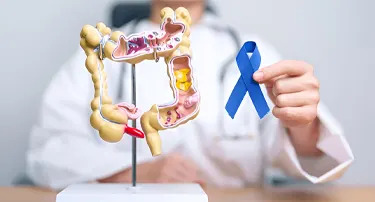

From Diagnosis To Treatment: Navigating Common Gastrointestinal Disorders

Your gut plays a big part in how you feel day-to-day. If your intestines or stomach isn't working, everything from your energy level to your mood suffers.

Common Gastrointestinal Diseases And How To Address Them

The gastrointestinal (GI) system plays a vital role in your overall health, helping the body digest food, absorb nutrients, and eliminate waste. When something goes wrong in the GI tract, it can lead to a variety of gastrointestinal issues that affect your quality of life.